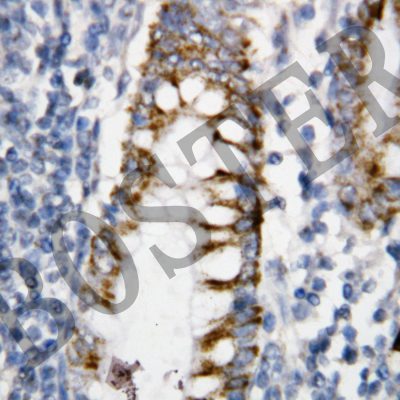

IHC analysis of BCL2 using anti-BCL2 antibody (BA0412).

BCL2 was detected in a paraffin-embedded section of human rectal cancer tissue. Biotinylated goat anti-rabbit IgG was used as secondary antibody. The tissue section was incubated with rabbit anti-BCL2 Antibody (BA0412) at a dilution of 1:200 and developed using Strepavidin-Biotin-Complex (SABC) (Catalog # SA1022) with DAB (Catalog # AR1027) as the chromogen.